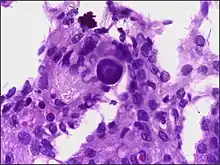

Micrograph of a psammoma body in the centre of the field in a meningioma of brain. H&E stain.

Histologically, meningioma cells are relatively uniform, with a tendency to encircle one another, forming whorls and psammoma bodies (laminated calcific concretions).[17] As such, they also have a tendency to calcify and are highly vascularized.